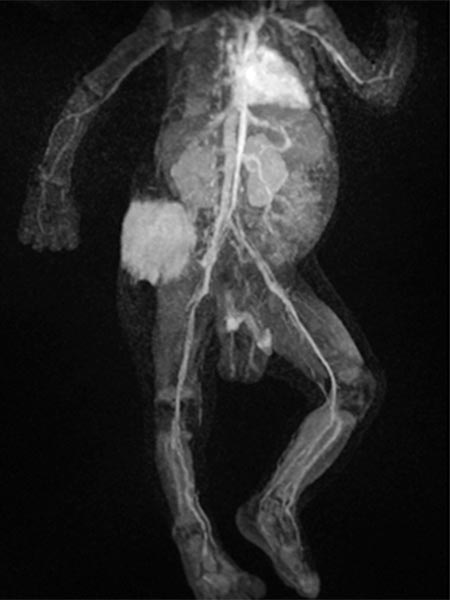

In view of massive coagulopathy prohibiting open surgery in this location and lack of improvement with drug therapy and replacement of platelets and coagulants alone, the decision was made to embolize the hypervascularized tumor. Digital subtraction angiography (DSA) shows the highly vascularized tumor supplied mainly from the right superior gluteal artery.

The tumor shows the typical tumor blush with diffuse, strong contrast enhancement on DSA after super-selective catheterization with the microcatheter.

Via the microcatheter, the tumor is now gradually embolized super-selectively with particles 150 microns in size via the supplying arterial branches.

In the control DSA, the main part of the tumor has now been successfully embolized and cut off from the circulation. Only very cranial tumor-supplying branches remained at this stage of the embolization.

These very cranial parts are now also catheterized super-selectively with the microcatheter and embolized with particles. For better navigation of the microcatheter, the vessels from a previous injection are electronically overlaid by the computer (so-called “overlay display”, white in the image).

In the final control angiography with long series after injection into the right common iliac artery, the tumor is completely devascularized. The unaffected, physiological arterial branches of the surrounding tissue are all preserved. Thus, the tumor is completely eliminated from the circulation. Activation of coagulation and consumption of platelets in the tumor has stopped.